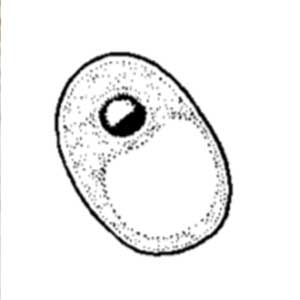

Les kystes de Iodamoeba butschlii sont ovalaires, à noyau rond, de diamètre moyen à grand, avec un nucléole large central à périphérique ; ce dernier n’est cependant pas toujours visible. Ils sont caractérisés par une vacuole iodophile volumineuse, excentrée, qui se colore franchement au Lugol, apparaissant brun-acajou. Ils mesurent 5 à 20 μm de longueur (Euzéby, 2008).

Les kystes de Iodamoeba butschlii sont en général facile à mettre en évidence par coloration de la vacuole iodophile au Lugol. Le diagnostic différentiel comprend les amibes de taille petite à moyenne dont les formes immatures d’Entamoeba histolytica qui peuvent aussi présenter une vacuole iodophile (Euzéby, 2008). Néanmoins, ces kystes immatures sont arrondis, ils présentent un à quatre noyaux de type Entamoeba, la vacuole iodophile, si elle existe, est moins colorée au Lugol, et ils possèdent des cristalloïdes que n’ont pas les kystes de Iodamoeba butschlii (Euzéby, 2008). Ces détails sont davantage visibles par coloration au trichrome ou à l’hématoxyline ferrique.